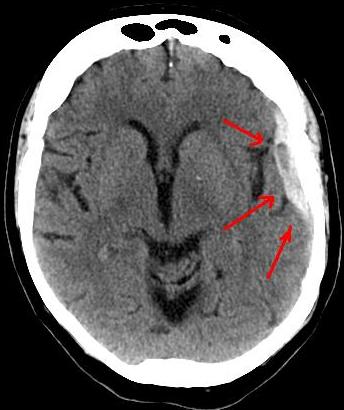

The whiplash was so severe that despite the impact being front on, a bleed on the surface of my brain was discovered at the back of my skull.

It wasn't until my family doctor booked a scan for me, 11 days after the incident, that we discovered what was going on.

Her words reverberate in my head every day: "You have a bleed on the brain".